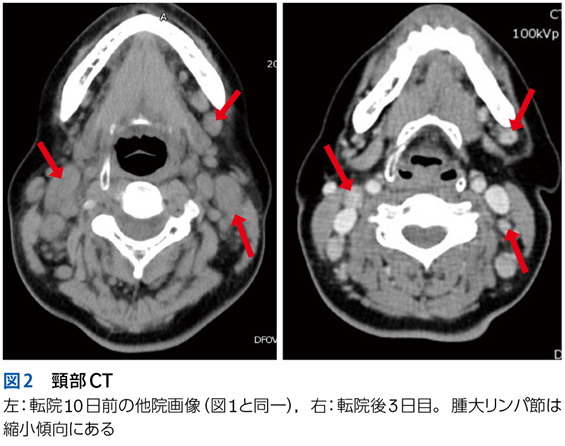

▶ こちらは初期評価不十分のまま多数の介入がなされたケースである。患者が呈している「プロブレム」をまとめて,「皮疹,肝機能異常,腎障害,汎血球減少を伴う遷延性発熱」とフレーミングし,たとえば血管内リンパ腫や血球貪食を伴う成人スティル病などを考えることも可能だが,現在の症状や検査異常(の一部)は抗菌薬をはじめとした介入の副作用として生じているのかもしれない。すべてのプロブレムが一元論で説明されない可能性も考慮したフレーミングも用意するのが謙虚な態度だろう。